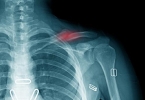

• 胸腔右侧里面隐隐作痛怎么回事

胸腔右侧里面隐隐作痛可能与肋软骨炎、胸膜炎、胆囊疾病、肌肉拉伤、带状疱疹等原因有关,可通过休息观察、药物治疗、影像学检查等方式缓解。建议及时就医明确病因,避免延误治疗。1、肋软骨炎肋软骨炎是胸痛常见原 ...